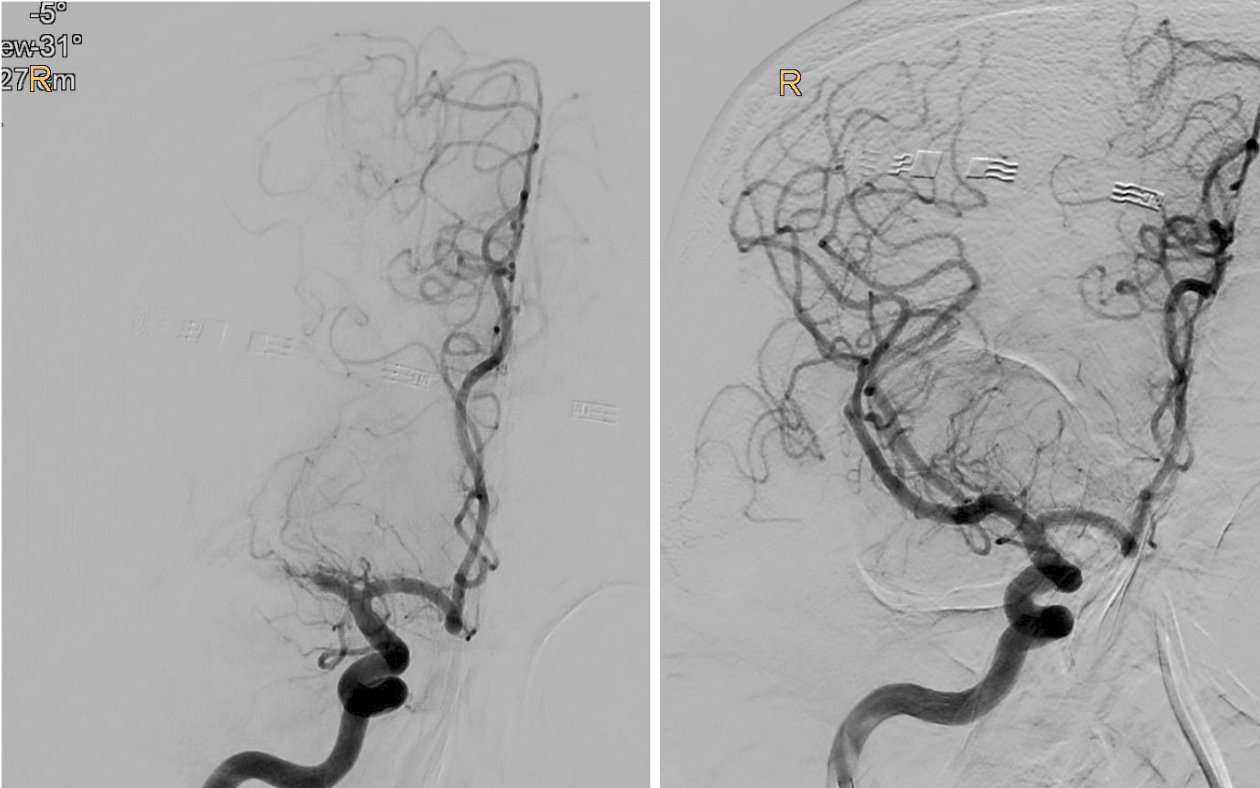

„Bei der Thrombektomie bringen wir mit einem Spezialkatheter von der Leiste ausgehend einen Stent an der Stelle des Gehirns ein, wo das Gerinnsel sitzt. Mit einer Saugvorrichtung wird das Blutgerinnsel dann zusammen mit dem Stent herausgezogen. Das Ganze passiert unter Röntgenkontrolle und bedarf viel Erfahrung“, erklärt Gizewski den sensiblen Vorgang. Vor 2015 wurde eine Thrombektomie standardmäßig meist nur durchgeführt, wenn eine Thrombolyse – medikamentöse Auflösung des Gerinnsels – bei den jeweiligen Patient:innen nicht durchgeführt werden konnte. Die großen Studien 2015 konnten zeigen, dass Patient:innen im frühen Stadium sehr von der Thrombektomie profitieren. Im Zuge der TENSION-Studie untersuchten die Expert:innen nun die Effektivität der Thrombektomie bei Schlaganfall-Patient:innen, deren Gehirn schon schwer geschädigt war.

„Bei einem Schlaganfall zählen einerseits Zeit und andererseits die noch verbliebene Sauerstoffversorgung des Gehirns, welche bei den Patient:innen unterschiedlich ausfällt. So genannte Kollaterale, Gefäß-Querverbindungen, können die Durchblutung noch einige Zeit aufrechterhalten. Je weniger solcher Kollateralen vorhanden sind, desto weniger Zeit hat man. Doch auch wenn schon Gewebe untergegangen ist, kann man noch etwas retten, wenn man thrombektomiert. Das konnten wir jetzt mit der TENSION-Studie zeigen“, berichtet Gizewski. Viele der Patient:innen könnten trotz der bedrohlichen Ausgangssituation jetzt wieder ein eigenständiges Leben führen. Nachdem sich der Erfolg der Katheter-Behandlung (insgesamt 125 Patient:innen) in der randomisierten Studie im Vergleich zur besten konservativen medizinischen Behandlung (128 Patient:innen) schnell gezeigt hatte, wurde die Studie frühzeitig beendet.